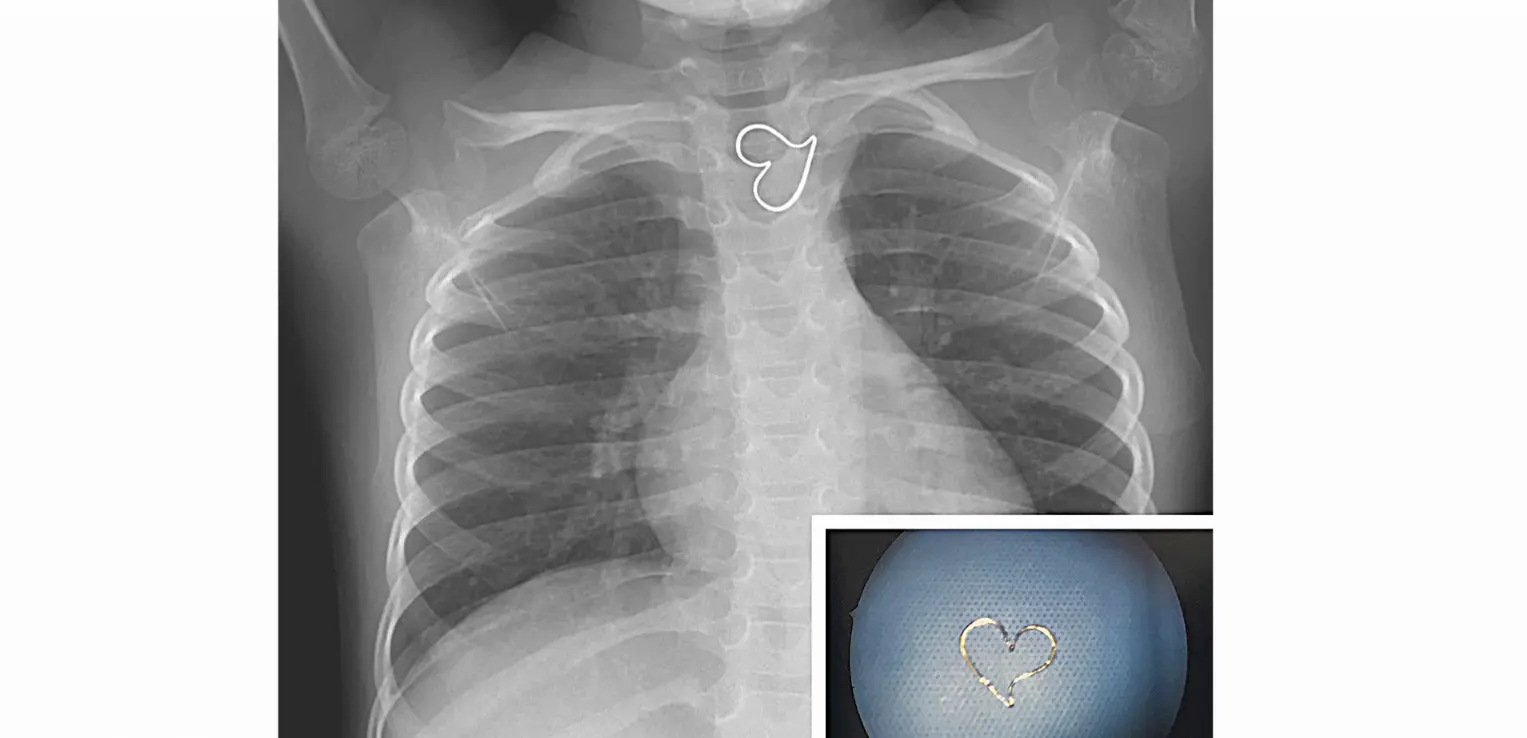

L'amour, c'est parfois un peu étouffant... Et c'est en pratique, ce qui a failli arriver à une fillette de Californie qui a ingurgité un pendentif en forme de coeur. Explications.

Le coeur en métal coincé en haut du thorax, dans l'oesophage, comprimait en partie la trachée de l'enfant.

La petite fille n'avait aucune douleur particulière. Mais comme le pendentif semblait coincé et était en position inchangée sur plusieurs radiographies, les médecins ont pris la décision d'intervenir. Ils ont donc retiré à l'aide d'un fibroscope le petit pendentif doré, qu'ils ont ensuite rendu à la propriétaire.